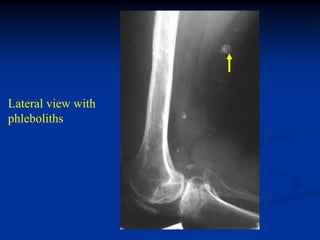

Case #585

36 year female with

Muffucci’s syndrome

Lateral view showing

phleboliths

Opposite femur

Lateral view with

hemangioma